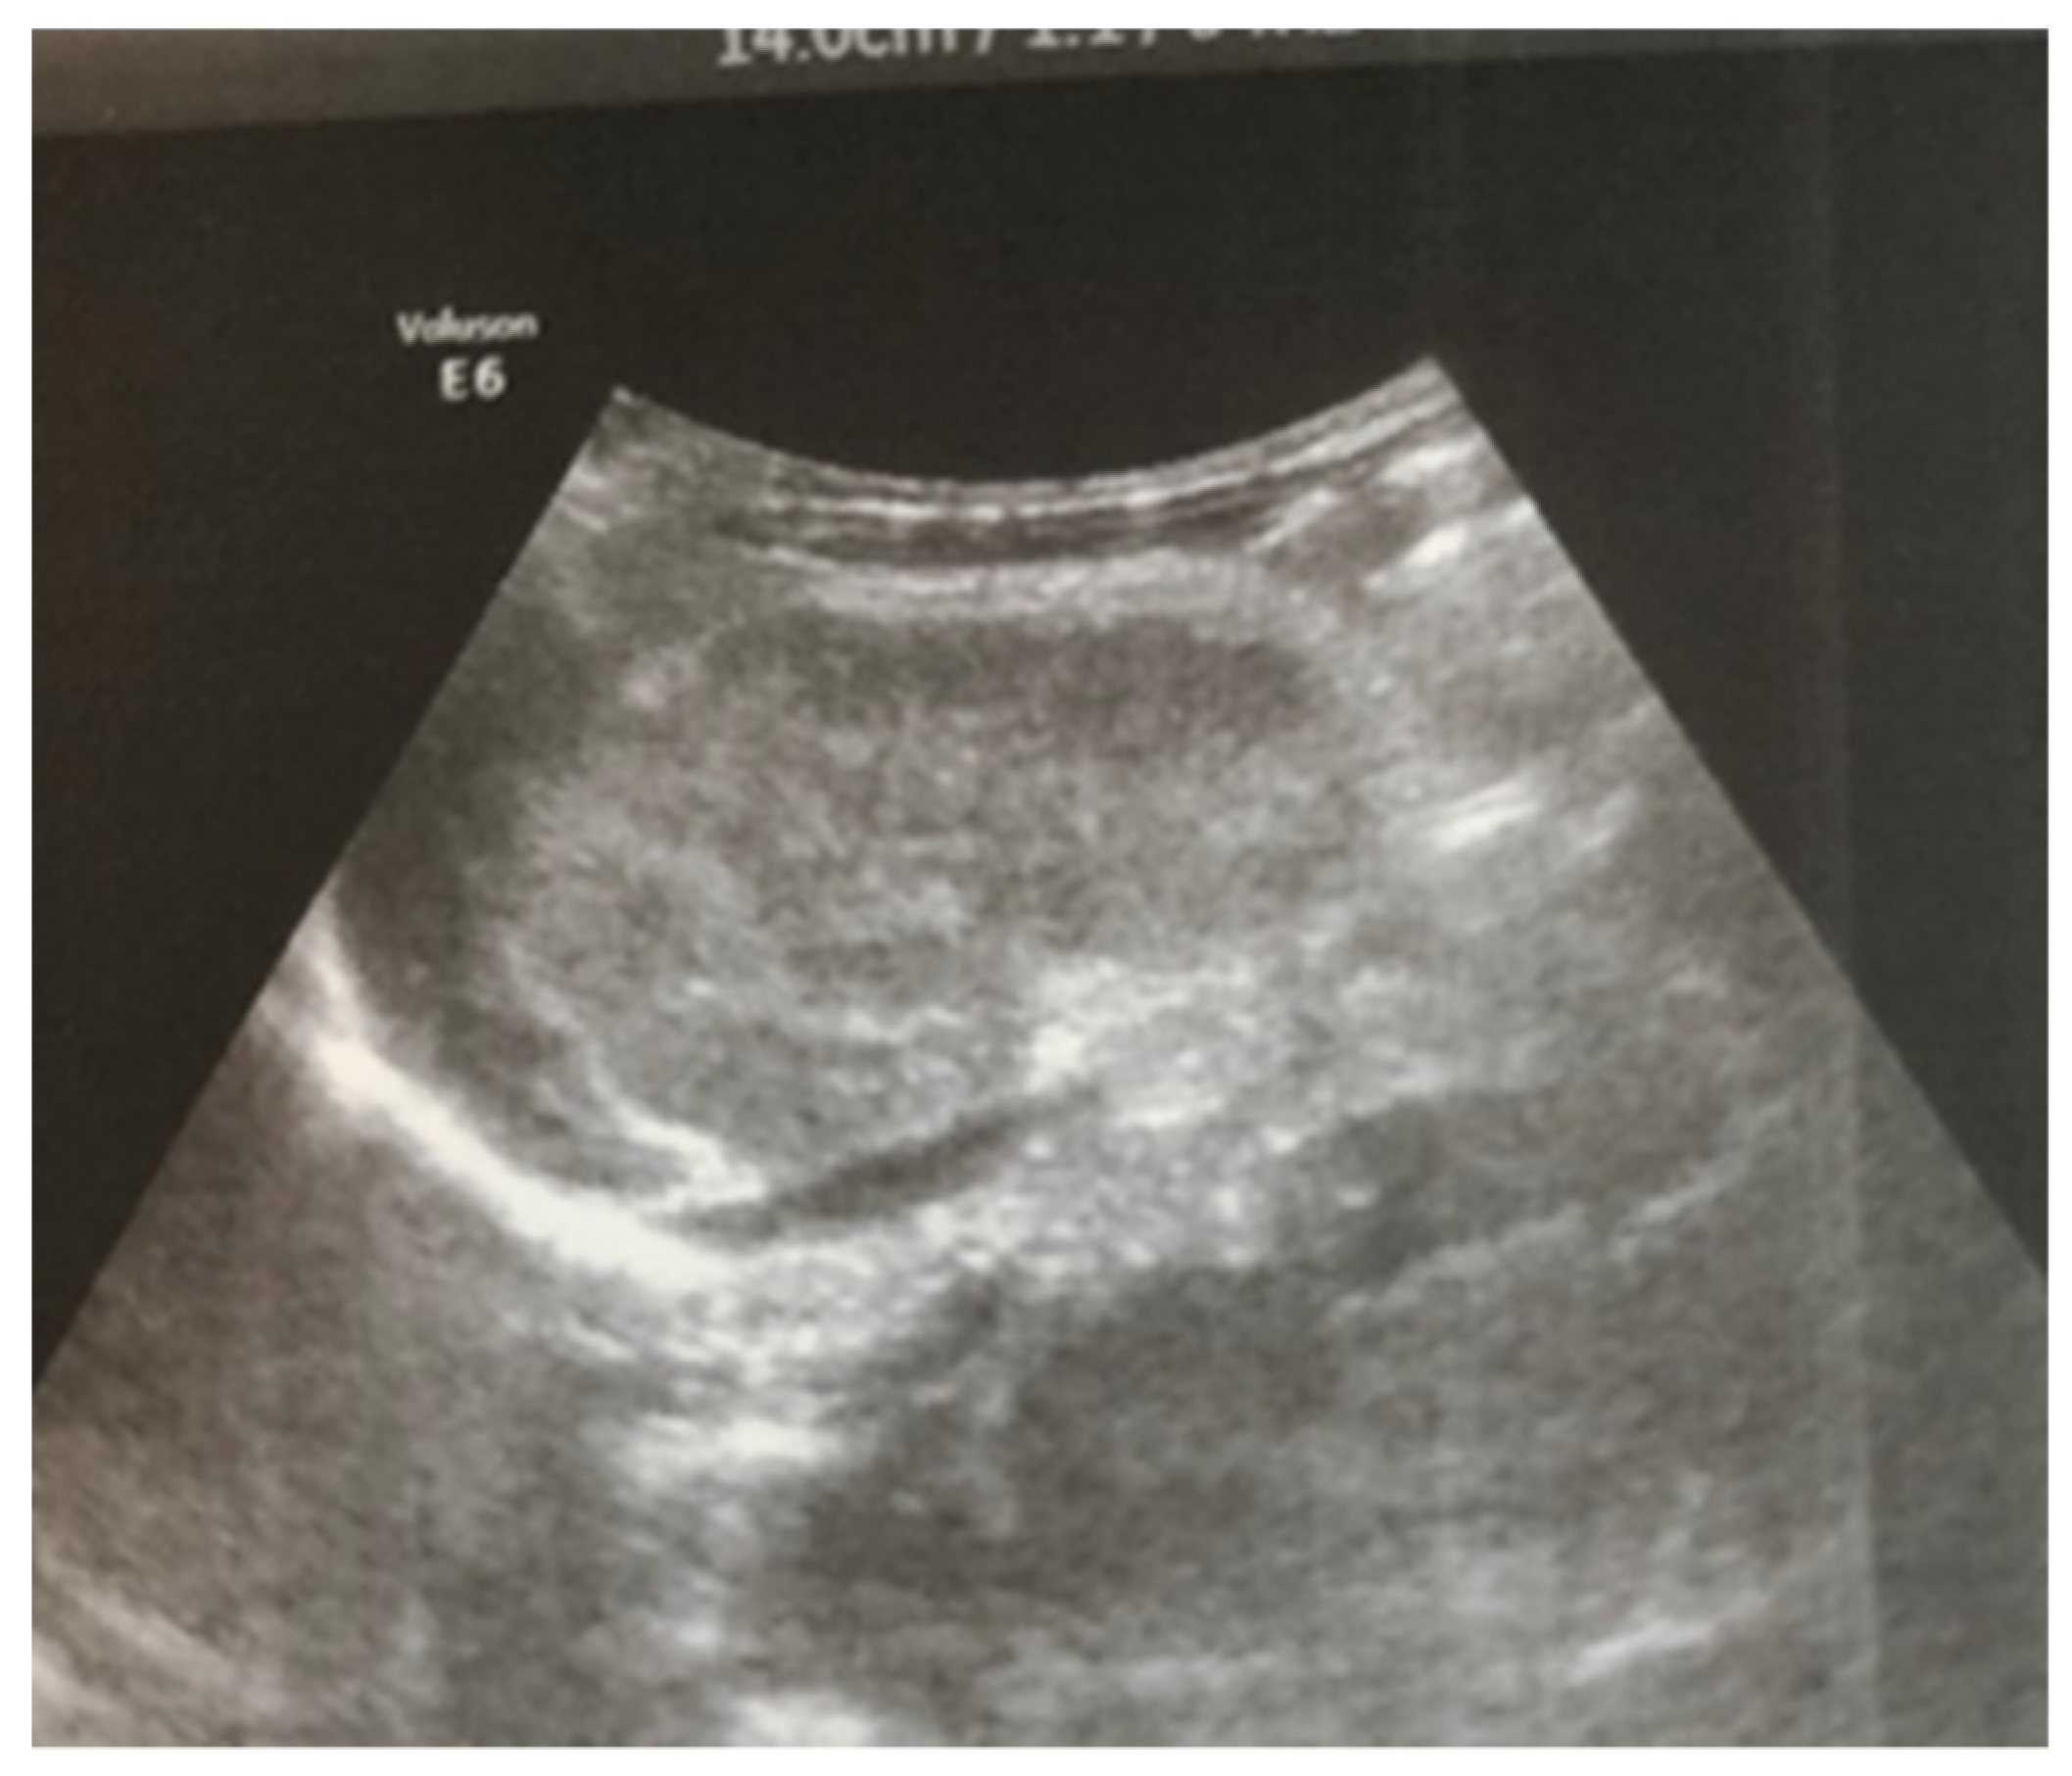

After admission to the NICU, the neonate was found febrile, with symptoms of multiple organ failure: respiratory system failure requiring treatment with Curosurf and mechanical ventilation; renal failure with symptoms of oliguria, macroscopic hematuria, and an increase in nitrogen waste products; the manifestation of neurological symptoms—muscular hypertonia and hyperreflexia, increased convulsive readiness with frequent spontaneous and provoked clonuses of the limbs. The blood tests revealed inflammatory activity—increased CRP and evidence of early nonconjugated hyperbilirubinemia. An abdominal ultrasound examination, performed 2 h after birth, found an enlarged right kidney with a longitudinal size of 6.1 cm, swollen parenchyma with a thickness of 1.8 cm, and increased echogenicity with the presence of interlobar hyperechogenic spikes—an image characteristic of the early phase of renal vein thrombosis. The left kidney—with a longitudinal size of 4.1 cm—preserved the topic, size, and echogenicity of the parenchyma, without drainage disorders, see Figure 1 and Figure 2.

Figure 2. Left kidney image taken in the 2nd hour after birth—the topic, size, and echogenicity of the parenchyma are preserved, without drainage disorders.